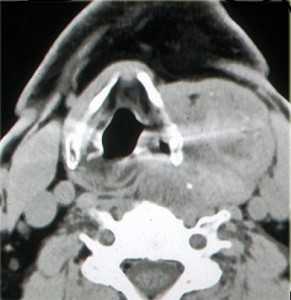

(Слева) МРТ Т1ВИ FS с КУ, аксиальная проекция. Крупная шваннома в нижней части шеи справа, которая лежит на средней лестничной мышце. Отмечается неравномерное накопление контраста по периферии опухоли. Центральная область, не накапливающая контраст, представляет собой участок кистозной дегенерации. При поражении нижних шейных лимфоузлов патологический очаг обычно расположен медиальнее, возле внутренней яремной вены.

(Справа) MPT Т2ВИ, аксиальная проекция. В нижней части шеи визуализируется шваннома сигнал гетерогенный гиперинтенсивный. Опухоль, расположенная в паравертебральном пространстве, раздвигает и деформирует переднюю и среднюю лестничные мышцы.